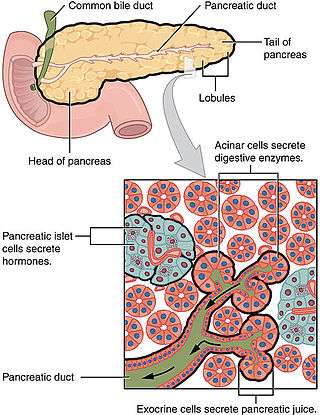

The many types of pancreatic cancer can be divided into two general groups. The vast majority of cases (about 99%) occur in the part of the pancreas which produces digestive enzymes, known as the exocrine component. There are several sub-types of exocrine pancreatic cancers, but their diagnosis and treatment have much in common. The small minority of cancers that arise in the hormone-producing (endocrine) tissue of the pancreas have different clinical characteristics. Both groups occur mainly (but not exclusively) in people over 40, and are slightly more common in men, but some rare sub-types mainly occur in women or children.[17][18]

Exocrine cancers

The exocrine group is dominated by pancreatic adenocarcinoma (variations of this name may add "invasive" and "ductal"), which is by far the most common type, representing about 85% of all pancreatic cancers.[4] Nearly all these start in the ducts of the pancreas, and pancreatic ductal adenocarcinoma is often abbreviated as PDAC.[19] This is despite the fact that the tissue from which it arises – the pancreatic ductal epithelium – represents less than 10% of the pancreas by cell volume.[20] This cancer originates in the ducts that carry secretions (such as enzymes and bicarbonate) away from the pancreas. About 60–70% of adenocarcinomas occur in the 'head' of the pancreas.[4]

The next most common type, acinar cell carcinoma of the pancreas, arises in the clusters of cells that produce these enzymes, and represents 5% of exocrine pancreas cancers.[21] Like the 'functioning' endocrine cancers described below, acinar cell carcinomas may cause over-production of certain molecules, in this case digestive enzymes, which may cause symptoms such as skin rashes and joint pain.